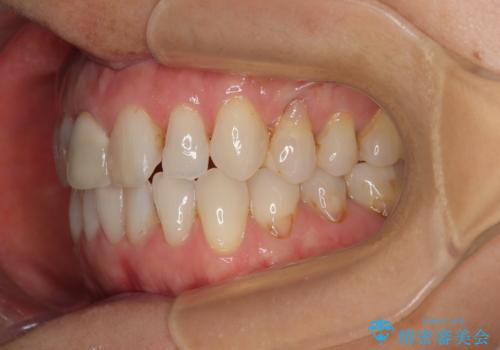

- 前歯のデコボコと口を開けたときに見える銀歯を気にして来院された患者様です。

ある程度デコボコが解消されれば大丈夫とのことで、インビザライン・モデレートパッケージを利用して歯列を整えて行くこととしました。

矯正治療後に銀歯をセラミッククラウンなどに置き換えていくと、どうしても後戻りを起こしてしまうため、矯正治療が概ね終了した時点で銀歯を全てセラミックとし、最後に仕上げでインビザラインにを用いて細かいデコボコを改善していくこととしました。